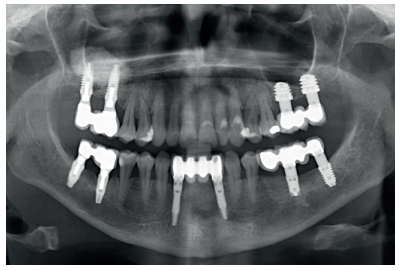

Back in 2007, the therapeutic protocol for these cases was very different (Figures 5-7), with short implants without full development – and without studies demonstrating the importance of diameter over implant length – efforts were focused on the search for anchorage by implant length instead of looking for the bicortical (vestibular-lingual) stability that short and wide implants perform. During this time, the failure of molars 46 and 47 also occurred; these were also extracted and replaced with dental implants.

After 4 years, the second and third quadrant molars began to have excessive mobility and serious periodontal problems, so it was decided to remove them and regenerate the alveoli with PRGF-Endoret. Once the area was regenerated (a month and a half later), a conebeam was performed to evaluate the residual bone volume. It can be seen how there was an uneven bone crest with areas of 3.3 mm in height up to a maximum of 7 mm (Figures 9 and 10). On this occasion, due to the protocol change described above, we opted for the direct insertion of extra-short implants, since the surgical protocols to address this type of situation in 2011 varied substantially, with these implants being a first-line tool for the treatment of this type of atrophy (Figure 11). Two extra-short implants were selected (5.5 mm diameter x 6.5 mm length for tooth 26, and 6 mm diameter x 5.5 mm length for tooth 27).